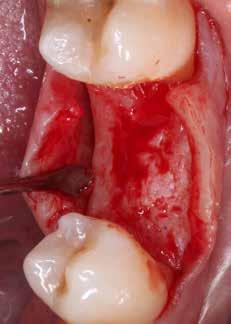

tel alapján az implantáció elvégezhető kiegészítő csontpót lás nélkül, de az állcsontgerinc sorvadt, így csak egy keskeny implantátummal biztosítható a megfelelő pozicionálás Ilyen esetben fontos, hogy tartsuk az előre meghatározott pozíciót, egy kis eltérés is azt eredményezheti, hogy a buk kális vagy lingvális csontfal túl vékony lesz az implantátum mellett Egy 3,5 mm átmérőjű és 10 mm hosszú Megagen AnyRidge implantátumra esett a választásunk Érdemes fi gyelembe venni, hogy a 3,5 mm átmérőjű implantátum prog resszív menetemelkedéssel rendelkezik, és a legszélesebb menetnél 3,5 helyett 3,9 mm a tényleges átmérője, míg a teste csak 2,8 mm széles Ezzel az implantátummal kiváló primer stabilitás érhető el A műtéthez sebészi sablont terveztünk R2 Gate programmal, ezzel a tervezett pozíciót is tartani tudjuk, és a páciens számá ra is egy rendkívül gyors, lebenyképzéssel nem járó műtétet biztosíthatunk A tervezéshez szükségünk van egy intraorális scan-re, vagy egy hagyományos lenyomatvétel és modellké szítés után bescannelt modellre, valamint egy CBCT felvétel re� A CBCT felvételt és a digitális modell �stl file-ját importáljuk a programba, majd ezután a meglévő fogak és a CBCT fel vételen is látható lágyrész képletek segítségével, egymásra igazítjuk őket Ha a két file tökéletesen fedi egymást, akkor egy kompozit modellt kapunk, amelyen a szájüregi képletek, a fogak, valamint a csontkínálat és a csontban futó anatómi ai képletek is megtalálhatóak� A tervezés következő lépése, hogy alsó állcsont esetén kijelöljük a n alveoláris inferior-t, és ezt rögzítjük a digitális modellen Ezután kiválaszthatjuk az implantátum méretét, típusát, és pontosan beállíthatjuk a helyzetét A pozicionáláshoz segítséget nyújthat, akár egy technikus által előre elkészített, digitális wax up, akár a prog ramban generált wax up, mely a modellre vetíthető, így lát hatjuk például, hogy hol lenne a tervezett pótláson a rögzítő csavar helye Miután befejeztük a tervezést, lehetőségünk van a projektet exportálni a R2 Ware nevű programba, ahol néhány kattintás segítségével megkapjuk a sebészi sablon tervét, amelyet már küldhetünk is a 3D nyomtatóra Lehetőségünk van még egy olyan emulált modellt is exportálni, amelyen az implantátum hely zete is rögzítve van, mintha a már behelyezett implantátumról vettünk volna lenyomatot Ennek alapján, a labor már a műtétet megelőzően el tudja készíteni az ideiglenes pótlást, amely mini mális korrekcióval, a műtétet követően azonnal be is helyezhető A műtét A műtéti sablont a nyomtatás után ki kell dolgozni, ezt a tech nikus, vagy mi – ha saját nyomtatónk van – elvégezhetjük egy gipszmodell vagy egy nyomtatott modell segítségével Ezután mi 70%-os alkohololdatba áztattuk, mivel az általunk használt sablon anyaga nem alkalmas autoklávban történő Asterilizálásra�szájüregben ellenőriztük, hogy a sablon pontosan illeszke dik-e, ezt a sablonra készített, ellenőrző ablakok segítségével könnyen megtehetjük Az implantátum helyének előkészíté séhez speciális implantációs tálcát és fúrókat használhatunk� A R2 sablonhoz való fúrók tövét úgy alakították ki, hogy pon tosan illeszkedjen a nyomtatott perselybe, így nem kell szűkí tőt helyeznünk a sablonba Az implantáció során, sablon nélkül is fontosnak tartom a lassú fordulaton történő fúrást Sablon használatnál ez különösen fontos, hiszen a hűtővíz nehezebben jut el a hű tendő területre Ez csak megfelelően éles fúrókkal valósítható Ameg3,5 mm AnyRidge implantátum magja 2,8 mm, és a bal alsó második premoláris fog területen a csonttípus D2 volt, ezért a 3,3 mm átmérőjű Cortical Drill volt az utolsó fúró, amit hasz náltam az előkészítéshez� Az implantátum behelyezése egy speciális behajtóval törté nik, amely a kézidarabhoz és a nyomatékkulcshoz is csatla koztatható, a rajta lévő jelölések segítik az elfordulásgátló helyzetének és az implantátum mélységének a kontrollálását� Az AnyRidge-re jellemző, magas primer stabilitást itt is meg figyelhettük, a nyomaték a behelyezés során 45 Ncm-t ért el, ez alkalmassá tette az esetet arra, hogy azonnali, ideiglenes

koronával lássuk el a frissen behe lyezett implantátumot Az ideiglenes korona a R2 Gate prog ramból előzetesen exportált stl file alapján, CAD-CAM technológiával faragott PMMA anyagból készült, kézben ragasztottuk össze egy elfor dulásgátlóval ellátott titán bázissal Hasznos tapasztalat, hogy az elfor dulásgátló nem illeszkedett tökéle tesen a beültetett implantátumba, egy kicsit elfordult ahhoz képest, így a koronát csak az elfordulás-gátló eltávolítása után tudtam behelyez ni Nehezen meghatározható, hogy pontosan mi okozta ezt az eltérést, de mindenképp egy kiküszöbölendő hibalehetőség a kézben, a modell segítsége nélkül történő összera gasztás� Érdemes egy néhány fogas kontroll modellt nyomtatni, amelybe beleilleszthetünk egy implantátum analógot, és ennek a segítségével el lehet végezni a korona és a fej össze Azkapcsolásátideiglenes koronát, a jó primer stabilitás ellenére, kivettem a ha rapásból A páciens elöl nyitott harapással rendelkezik, ezért a hát só fogai erősebb terhelést kapnak a funkciós mozgások során, nem akar tam kockáztatni a frissen behelye zett implantátum túlterhelését Az 1 hetes kontroll alkalmával a pá ciens arról számolt be, hogy még a műtét napján sem tapasztalt fájdal mat vagy bármilyen kellemetlensé get A környező íny gyulladásmentes és fájdalmatlan, varratszedésre nem volt szükség A beavatkozás során jó tapaszta latokat szereztem mind a R2 Gate rendszerrel, mind pedig a Megagen AnyRidge implantátummal kapcso latban Az, hogy a bemutatott rend szert hosszútávon hogyan tudjuk a legjobban beilleszteni az általunk végzett kezelések közé még további tapasztalatszerzést igényel